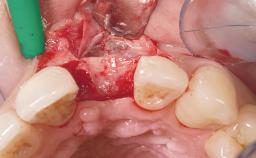

Immediate Placement of an Implant in a Maxillary Left Central Incisor Site

A 33-year-old female patient presented with an upper left central incisor that required extraction after a failed endodontic therapy. The tooth had been traumatized when the patient was a teenager and had undergone several endodontic treatments, including two apicectomy procedures. The patient was in good health and did not smoke. Clinical examination showed that the patient had a high lip line. In full smile, the gingival margins of the upper teeth were visible to the first molars. The gingival margins of central incisors 11 and 21 were only just showing. Examination of tooth 21 confirmed that the tooth was mobile and had hypererupted by 1 mm.

Socket Integrity Damage to one or more bone walls

Bone Volume Damage to one or more socket walls